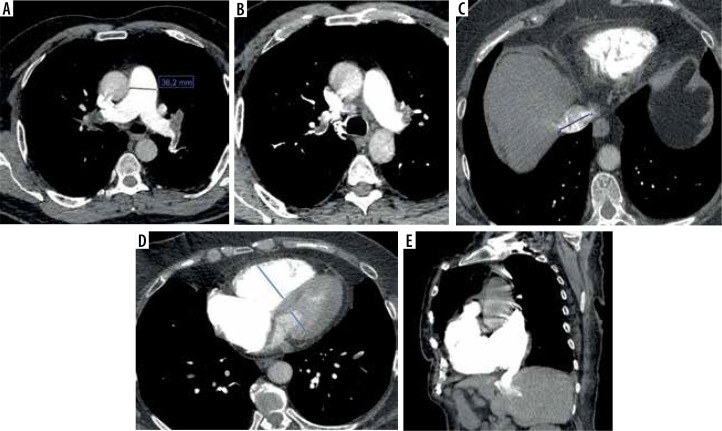

Purpose: Late diagnosis is associated with high mortality rates in acute pulmonary embolism (PE), so early diagnosis and risk assessment are crucial. We aim to evaluate computed tomography pulmonary angiography measurements to identify relationships with 30-day mortality in patients with pulmonary embolism. This study investigated the utility of computed tomography pulmonary angiography (CTPA) measures in determining 30-day PE-related mortality and identified various echocardiographic, demographic, and clinical variables that were independently associated with short-term mortality in patients with acute PE.

Material and methods: This retrospective study examined data from July 2018 to April 2023. A total of 118 patients were included in the study. Clinical and demographic characteristics, laboratory findings, echocardiographic data, and CTPA images were retrieved from the electronic database and patient charts.

Results: The rate of 30-day mortality was 14.41%. Deceased patients were significantly older than survivors (73.53 ± 14.17 vs. 60.23 ± 17.49 years; p = 0.004), but the sex distribution was similar. In multivariable logistic regression, having received radiotherapy for malignancy, high pulmonary artery obstruction index % (> 46.2), high left pulmonary artery diameter (> 23.9 mm), and high coronary artery calcification score (> 5.5) were independently associated with mortality.

Conclusions: These results reveal specific parameters that can assist acute PE management by enabling the identification of critical events. Despite promising results in predicting short-term mortality in acute PE, further prospective cohort studies are needed to confirm the results of the present study.